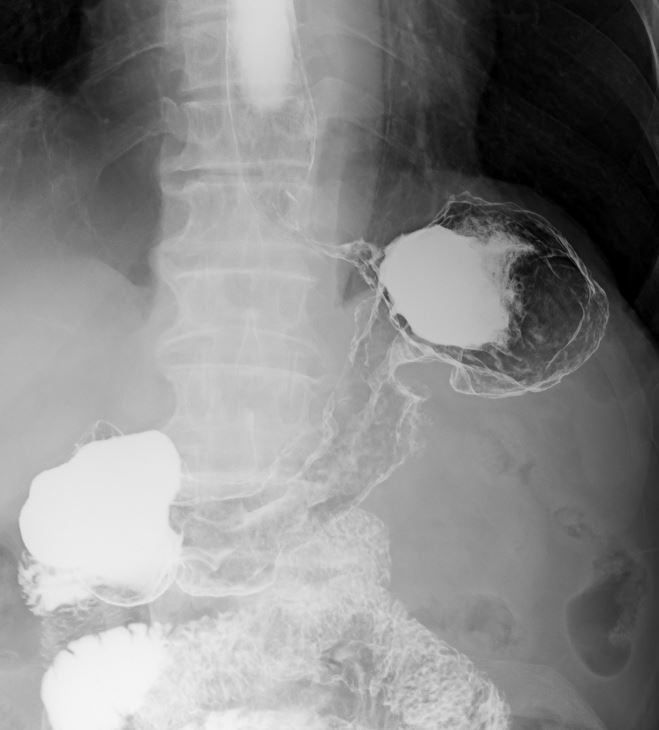

大腸造影検査は、造影剤を使って大腸の内部をX線で映し出し、ポリープや腫瘍、炎症などの異常を調べることができます。腸が重なり病変がわかりにくい場合は複数の角度からX線撮影し、それらの画像をコンピューターで立体的に再構成する断層撮影を行います。これにより、通常の撮影では見えにくい腸の重なりを分離して、より詳細で正確な画像が得られます。

大腸造影 |

大腸の断層画像 |